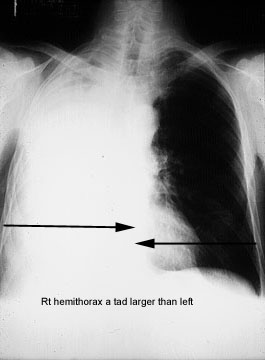

- Hemithorax

size is larger due to loss of negative pressure in

pleural space.